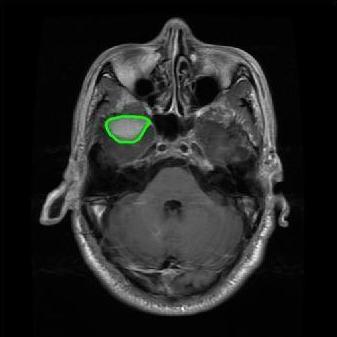

4.2 Comparison with brain tumor MR images segmentation

Brain tumor MRI images represent a critical challenge within the field of medical image analysis, making them a focal point of our research. Various level set models for image segmentation have been applied to brain tumor MRI images, and it is essential to consider the unique characteristics of these images. To validate the excellent performance of the RefLSM, we conduct segmentation comparison experiments on brain MR images and compute the Dice coefficient and Precision values for all evaluated models.

Fig. 4 displays the visual comparison results for segmenting eight brain tumor MR images between the RefLSM and three representative models: the RESLS [8765635], ALF[MA2019201], and L1 model[LIU2019193]. These images exhibit severe intensity inhomogeneity and noise attributable to inconsistent bias field and imaging equipment. The initial level set function (LSF) initialization was consistent across all models, as shown in Fig. 4 (a), which illustrates the initial placement of the zero level contour. For visual clarity, we included the ground truth in Fig. 4 (f). The segmentation outcomes from the RESLS, ALF, and L1 methods are presented in Fig. 4 (b), (c), and (d), respectively.

It is evident from the first and last columns of Fig. 4 (b) that the ALF model tends to become trapped in local minima under severe intensity inhomogeneity. Furthermore, segmentation results presented in the columns 1-4 of Fig. 4 (b) and (c) reveal that both the ALF and L1 models mistakenly segment small isolated or irrelevant regions due to the effects of irregular intensity patterns. Additionally, when weak boundaries are present, as seen in the 1st and 3rd columns of Fig. 4, the RESLS, ALF, and L1 methods fail to accurately identify object boundaries. Consequently, the zero level contours of these models deviate significantly from the objects throughout the level set evolution, causing drastic misalignment after further iterations.

In stark contrast, our proposed method exhibits greater robustness against images exhibiting severe intensity inhomogeneity and weak boundaries. The proposed prior constraint term effectively corrects for intensity inhomogeneity, while the proposed binary level set adeptly reduces noise during the segmentation process.

Overall, these findings demonstrate that the segmentation outcomes produced by our model are more accurate. Besides visual assessment, we calculate the Dice and Precision values of evaluated models for brain tumor segmentation in table 1. Based on these results, we draw a boxplot with scatterplot overlay, as shown in Fig. 6, which displays the data distribution and facilitates comparison of different models’ performance across various brain tumor MR images. We analyze the maximum, median, and minimum, which correspond to the best, median segmentation results, and worst segmentation results, respectively. It is clear that the RefLSM achieves more accurate segmentation results compared to the other models. Moreover, the smaller range of the RefLSM in the boxplot indicates robustness and stability to different images of the brain tumor.